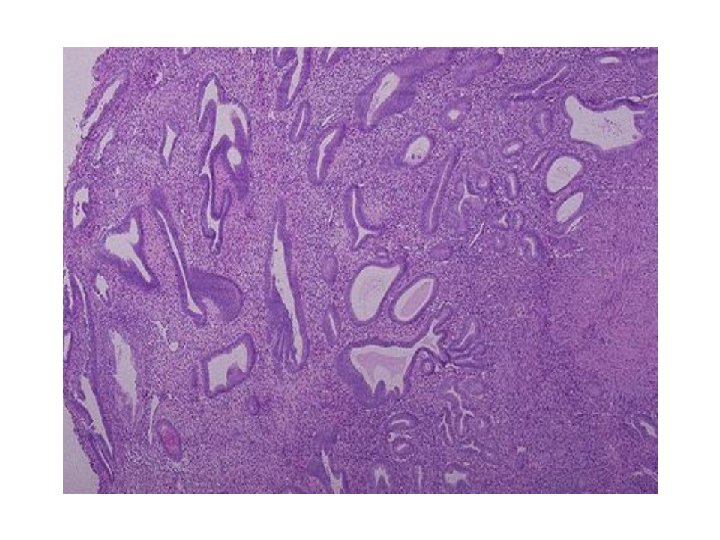

HİPERPLAZİ Hücre sayısında artış Çoğalma yeteneği olan hücrelerde görülen bir uyum yanıtı Hiperplazi ve hipertrofi birlikte görülebilir. Ör: Gebelikte uterus büyümesi Fizyolojik hiperplazi 1. Hormonal hiperplazi Pubertede meme, gebelikte uterus hiperplazisi 2 - Kompansatuvar hiperplazi Parsiyel hepatektomiden sonra KC rejenerasyonu Patolojik hiperplazi Aşırı hormonal stimülasyon hücreleri etkileyerek hiperplaziye yol açar. Endometrial hiperplazi

METAPLAZİ: • Olgun bir hücre türünün yerini, hücre hasarından korunma amacı ile, başka bir olgun hücrenin (hasara daha dayanıklı) alması • Kök hücrelerin genetik olarak yeniden programlanması ile gerçekleşir. • Fonksiyon bozukluğu ve irritasyonun uzun süreli olduğu durumda malign transformasyon riski oluşur.